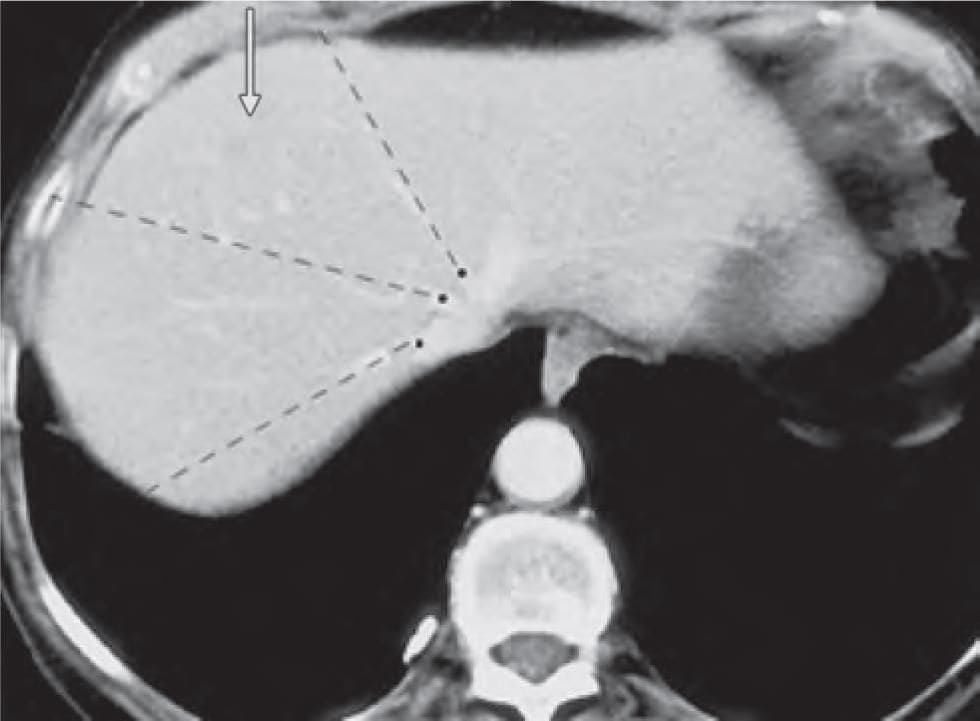

Liver is divided into eight segments according to Couinaud’s classification based upon. (AIIMS May 2019)

In CT scan of liver, identify the arrow marked segment: (INI-CET Nov 2022)